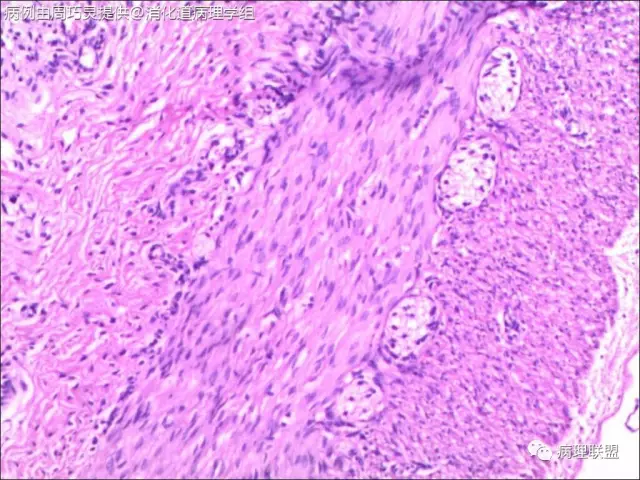

引产胎儿,小肠扩张,肠管回盲部以下直径<回盲部以上。取回盲部及升结肠肠壁镜检。(病例由周巧灵提供,致谢!)

@石雪迎 石老师,取的就是扩张肠管远端狭窄处,刚好就是回盲部。我在肠壁中见到比较多的神经节,但是里面很少见正常成熟的神经节细胞,应该是支持巨结肠的。不过,我不知道,胎儿时期肠壁正常的神经节是啥样子,所以,不太敢确定,还请老师指点。

@周巧灵 抱歉看错了,以为是结肠扩张。不知道是多大周数引产的胎儿?理论上4个月的胎儿肠神经丛就完成从近端到远端的分布,但直到出生,神经节里的都有不成熟的节细胞。您的图片里确实大部分都没有成熟神经元,但有的似乎不能排除有不成熟神经元,可以染NSE看看,如果还有,诊断HD就没有依据了。中华病理杂志曾经发表过何乐健教授等写的一篇HD病理诊断规范,尤其是有关取材的建议很实用,不妨参考一下